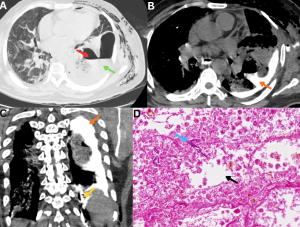

Fig 21: Case 1 -

Clinical history:

A middle-aged male with uncontrolled diabetes mellitus and recent corticosteroid exposure, a diagnosed case of disseminated mucormycosis, presented with fever and sepsis.

Figures A & B:

Figure A: Magnified ultrasound image demonstrates multiple hypoechoic lesions in the liver (red arrows).

Figure B: Axial contrast-enhanced CT (CECT) abdomen image demonstrates multiple hypodense, hypoenhancing lesions in the liver (green arrows), consistent with hepatic microabscesses.

......Case 2 -

A diabetic male with recent COVID-19 infection and corticosteroid exposure, a diagnosed case of disseminated mucormycosis, presented with persistent fever and abdominal pain.

Figures C & D:

Figure C: Magnified ultrasound image demonstrates multiple hypoechoic lesions in the spleen (orange arrows).

Figure D: Axial contrast-enhanced CT (CECT) abdomen image demonstrates multiple hypodense, hypoenhancing lesions in the spleen (yellow arrows), consistent with splenic microabscesses.